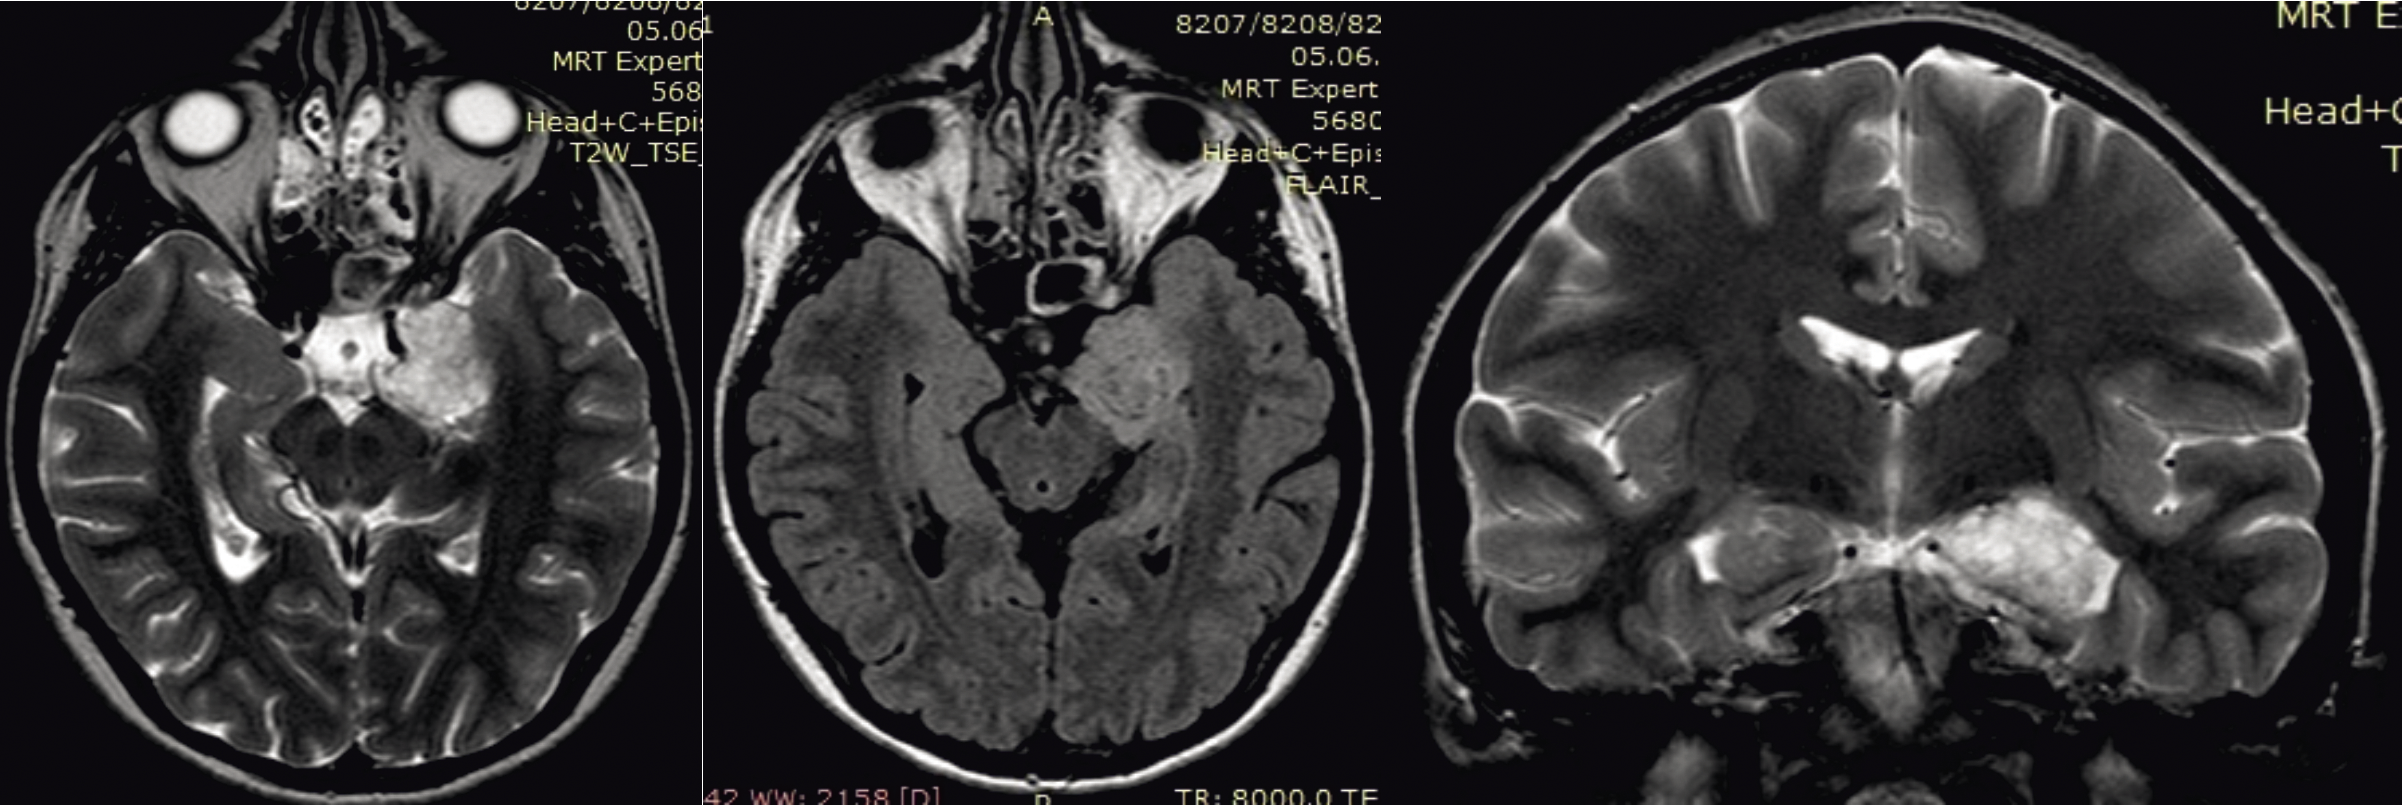

По данным МРТ больной до операции выявляется глубинное внутримозговое новообразование, поражающее левый гиппокамп, нижний рог левого бокового желудочка с распространением на ножковую цистерну (рис. 4).

Рис. 4. МРТ головного мозга с внутривенным контрастированием перед оперативным вмешательством. А: Т2-взвешенное изображение, аксиальная проекция на уровне патологического очага; Б: Т1-взвешенное изображение, аксиальная проекция на уровне патологического очага; В: Т2-взвешенное изображение, корональная проекция на уровне патологического очага